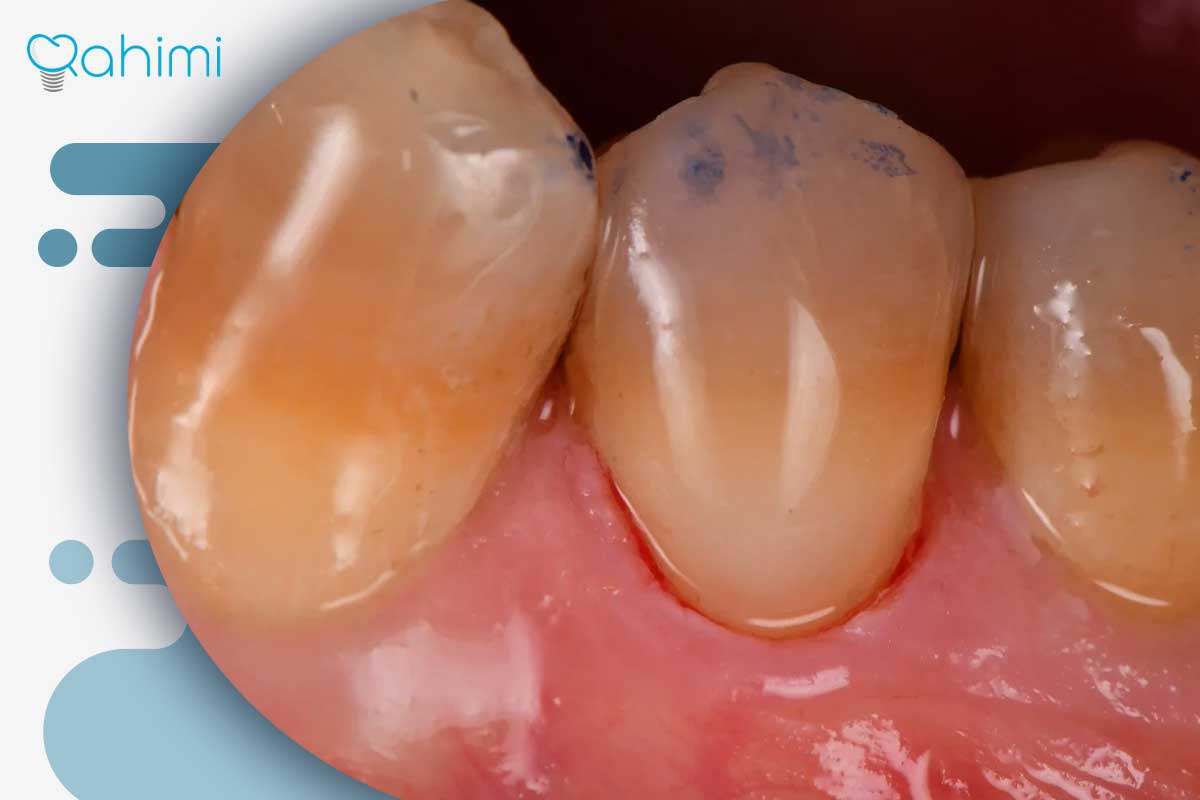

تشکیل پاکت لثهای و عمیق شدن حفرهها: هرچه مدت بیماری لثه طولانیتر باشد و کنترل پلاک ضعیفتر انجام شود، عمق پاکت افزایش مییابد، استخوان بیشتری از بین میرود و حفره لثهای از یک گودی خفیف به سوراخی عمیق تبدیل میشود. در این مرحله، بیمار ممکن است علائمی مانند بوی بد دهان، خونریزی هنگام مسواک، لقی دندان یا ترشح چرک تجربه کند. درمان معمولاً شامل جرمگیری عمیق، روت پلنینگ و در موارد پیشرفته جراحی لثه است.

پوسیدگی زیر خط لثه: گاهی علت حفرهای که روی لثه دیده میشود، پوسیدگی مخفی روی ریشه یا زیر لبه ترمیم قدیمی است. عواملی مانند ترمیمهای نامناسب، گیر غذایی بین دندانها، خشکی دهان و دسترسی دشوار به مسواک و نخدندان، میتوانند باعث این نوع پوسیدگی شوند. این پوسیدگیها با تخریب بافت سخت دندان و تحریک لثه، منجر به ایجاد گودی یا سوراخ در بافت لثه میشوند.

عقبرفتگی لثه و ایجاد فضای خالی: در تحلیل لثه، خط لثه به سمت ریشه پایین میآید و ریشه دندان نمایان میشود. اگر ریشه برجسته باشد یا خط لثه نامنظم شده باشد، این وضعیت به شکل گودی یا حفره در مرز لثه و دندان دیده میشود. دلایل شایع عقبرفتگی لثه شامل مسواکزدن محکم، بیماری لثه درماننشده، ناهنجاریهای مالاکلوژن و نازکی طبیعی بافت لثه هستند. تحلیل پیشرفته همراه با بیماری پریودنتال میتواند این گودیها را به پاکتهای عمیق تبدیل کند.